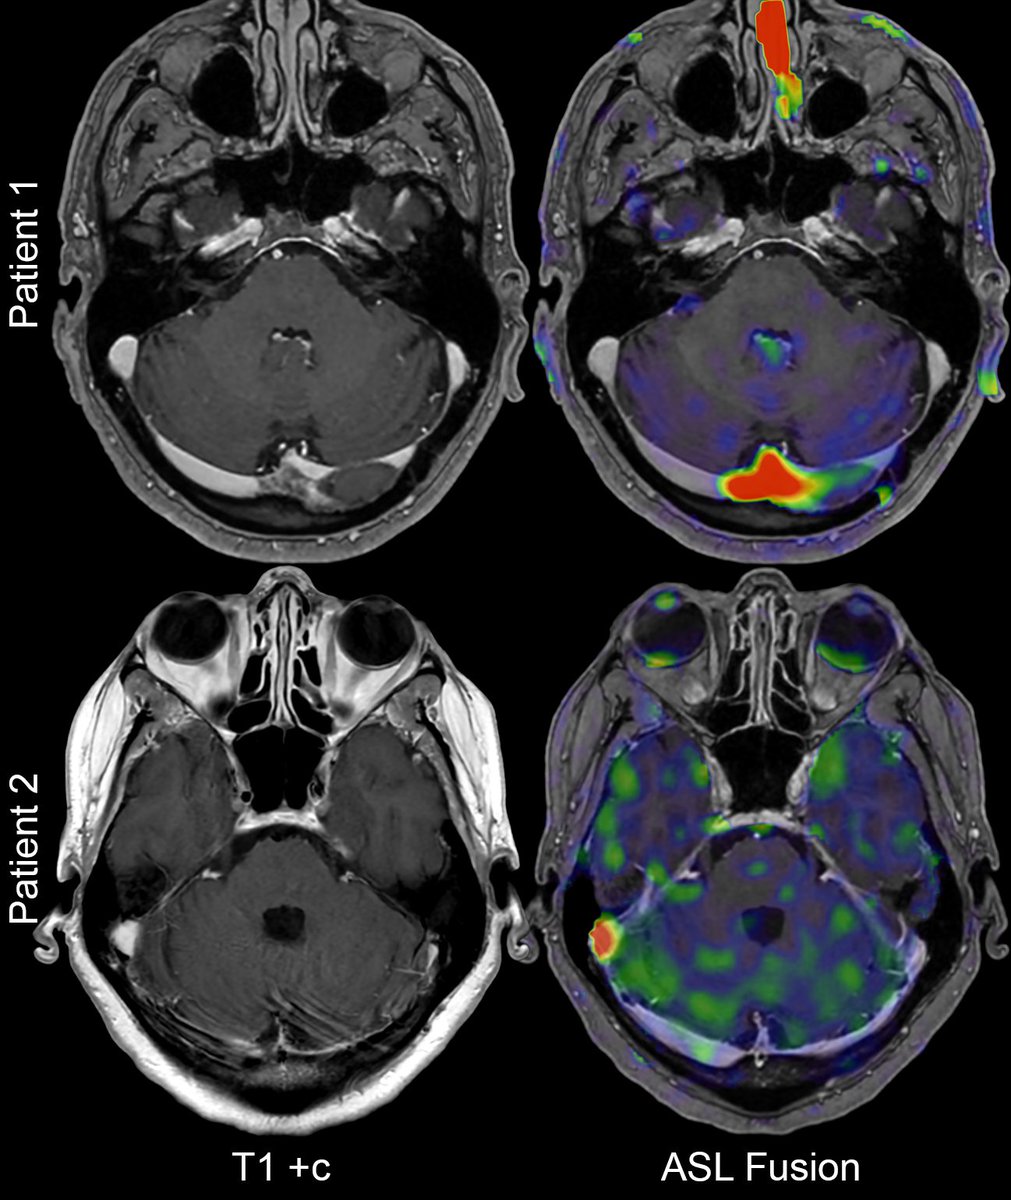

🎊 Our new study is now online in AJNR! While stroke research has focused on the infarct, we show using AI that non-infarct regions tied to brain plasticity and health also predict functional outcomes. @GregZ_MD @stanfordneuroi1 @StanfordRad @TheAJNR ajnr.org/content/early/…